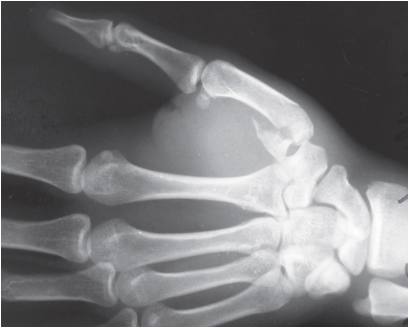

Sobre a lesão mostrada na figura, é CORRETO afirmar que